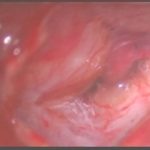

術中写真

摘出 前